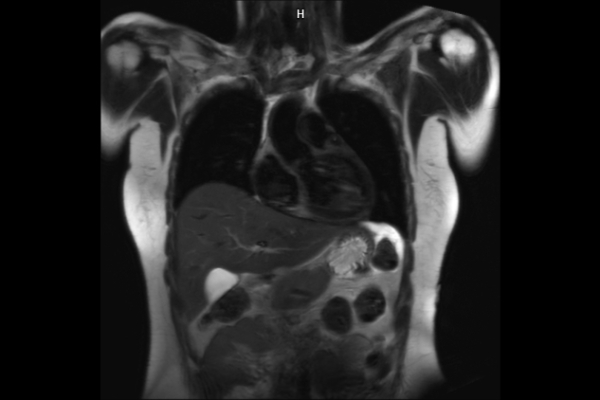

Wir verbinden modernste Medizin mit einer Atmosphäre, in der Sie sich sicher und gut aufgehoben fühlen. Klare Abläufe, Ruhe und Zeit für Sie stehen im Mittelpunkt jeder Untersuchung. CT- und MRT-Bilder ohne Wartezeit. Mit Photon-Counting-CT und 3-Tesla-MRT setzen wir auf in Kärnten einzigartige Technologien für außergewöhnlich detailreiche Bilder und besonders präzise Diagnosen. Die schonenden Verfahren eignen sich auch für Kinder und Jugendliche. Kurze Messzeiten, große offene Geräte und ein ruhiges Umfeld sorgen für eine angenehme Untersuchung und ein gutes Gefühl von Anfang bis Ende.

Detailbild MRT

MRT und CT

Entdecken Sie, welche CT- und MRT-Untersuchungen in unserer Radiologie für jeden Bereich Ihres Körpers möglich sind.

Wir bieten ein breites Spektrum an Untersuchungen an, von Standarduntersuchungen der Gelenke, Organe oder großflächigen Körperregionen bis zu Spezialuntersuchungen zum Beispiel des Herzen oder der Gefäße. Zusätzlich werden Angiographien (Darstellung von Blutgefäßen), Endometriose-Abklärungen und Mamma-Untersuchungen durchgeführt. Genauere Details können Sie der MRT/CT-Übersicht und der Preisliste entnehmen, oder Sie wenden sich direkt an unser Team, das Sie gerne zur passenden Untersuchung berät.